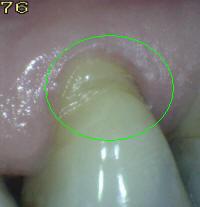

Código E:

Si la

superficie de la raíz

no puede ser visualizada

directamente como resultado

de la falta de la recesión

gingival,

entonces es

excluida. Ver imagen

inferior izquierda. Superficies

cubiertas completamente por

cálculos deben ser

removidos antes de

determinar el estado de

la superficie.